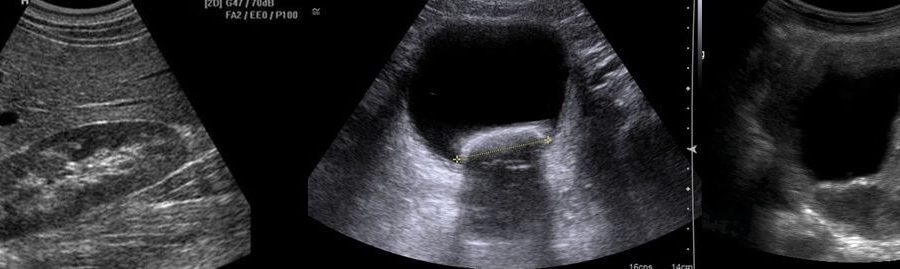

Urinary ultrasound can be performed with any complaints or during routine controls. Ultrasound methods are used when it is desired to evaluate the shape, size and position of the kidneys. In addition, this method is used when researching diseases such as kidney failure, hypertension and diabetes.

Urinary ultrasound is also requested to investigate whether there are stones, sand, masses or cysts in the kidney. While examining the abdomen of the patient, points such as thickening of the bladder wall and infection are also examined.

Urinary ultrasound procedures are used to detect problems in the kidneys and bladder. During the procedure, patients do not feel any pain or pain. Before a urinary ultrasound scan, patients should pay attention to some points.

In order to perform detailed imaging, the bladder must be full during ultrasound procedures, that is, the patient must be constricted with urine. For urinary ultrasound, the patient is asked to lie on his back or flat.

A detailed examination of the abdomen is performed by a specialist doctor or radiologist. The ultrasound results of the individuals are evaluated by the radiology specialist and reported.